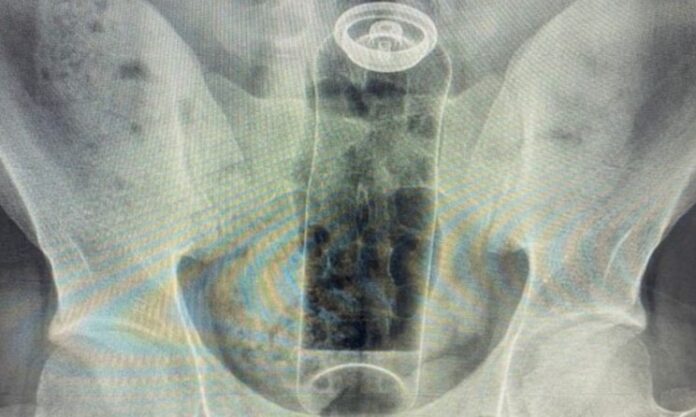

Um jovem de 19 anos precisou ser internado após ficar com um frasco de desodorante preso no reto. O caso foi compartilhado pelo cirurgião coloproctologista Daniel Brosco em suas redes sociais nesta segunda-feira (26), que aproveitou para alertar sobre os riscos de inserir objetos inadequados durante práticas sexuais.

De acordo com o especialista, o paciente relatou que o incidente ocorreu durante uma “brincadeira” sexual. O frasco acabou subindo para o reto e, após tentativas frustradas de retirá-lo em casa, ele buscou atendimento médico.

Brosco explicou que o intestino, por meio dos movimentos peristálticos — contrações involuntárias que deslocam o conteúdo intestinal —, combinado ao efeito de vácuo da região, pode “sugar” o objeto, dificultando sua remoção sem intervenção profissional.